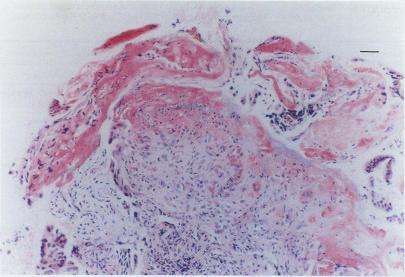

The first study of photodynamic therapy in the human gastrointestinal tract using 5 aminolaevulinic acid (ALA) induced protoporphyrin IX as the photosensitising agent is described. Eighteen patients with colorectal, duodenal, and oesophageal tumours were studied. After 30-60 mg/kg of ALA given orally, biopsy specimens of tumour and adjacent normal mucosa were taken 1-72 hours later. These specimens were examined by quantitative fluorescence microscopy for assessment of sensitisation with protoporphyrin IX. Ten patients were given a second dose of ALA a few weeks later and their tumours were treated with red laser light (628 nm). With 30 mg/kg ALA, the highest fluorescence values were detected in the duodenum and oesophagus, and the lowest in the large bowel. Doubling the ALA dose in patients with colorectal tumours gave protoporphyrin IX fluorescence intensities similar to those in patients with upper gastrointestinal lesions and improved the tumour:normal mucosa protoporphyrin IX sensitisation ratio. The treated patients showed superficial mucosal necrosis in the areas exposed to laser light. Six patients had transient rises in serum aspartate aminotransferases, two mild skin photosensitivity reactions, and five mild nausea and vomiting. In conclusion, photodynamic therapy with systemically administered ALA may be a promising technique for the treatment of small tumours and areas of dysplasia such as in Barrett's oesophagus.

本文描述了首例使用5-氨基酮戊酸(ALA)诱导原卟啉IX作为光敏剂在人体胃肠道进行光动力治疗的研究。研究了18例患有结直肠、十二指肠和食管肿瘤的患者。口服30 - 60mg/kg的ALA后,1 - 72小时后采集肿瘤及相邻正常黏膜的活检标本。通过定量荧光显微镜检查这些标本,以评估原卟啉IX的致敏情况。几周后,10例患者接受了第二剂ALA,并使用红色激光(628nm)治疗他们的肿瘤。给予30mg/kg的ALA时,在十二指肠和食管中检测到最高的荧光值,在大肠中最低。将结直肠肿瘤患者的ALA剂量加倍后,原卟啉IX荧光强度与上消化道病变患者相似,并提高了肿瘤与正常黏膜的原卟啉IX致敏率。接受治疗的患者在暴露于激光的区域出现浅表黏膜坏死。6例患者血清天冬氨酸转氨酶短暂升高,2例出现轻度皮肤光敏反应,5例出现轻度恶心和呕吐。总之,全身给予ALA进行光动力治疗可能是治疗小肿瘤和发育异常区域(如巴雷特食管)的一种有前景的技术。